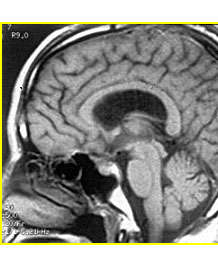

沈建康主任論文:顱內巨大動脈瘤的顯微外科手術治療

沈建康主任論文:鞍結節(jié)腦膜瘤的手術入路和技巧

(專家解讀)癲癇發(fā)病的因素有哪些?

侯增欣教授訪談:如何識別腦腫瘤早期信號?

侯增欣教授訪談:腦瘤究竟有多可怕?